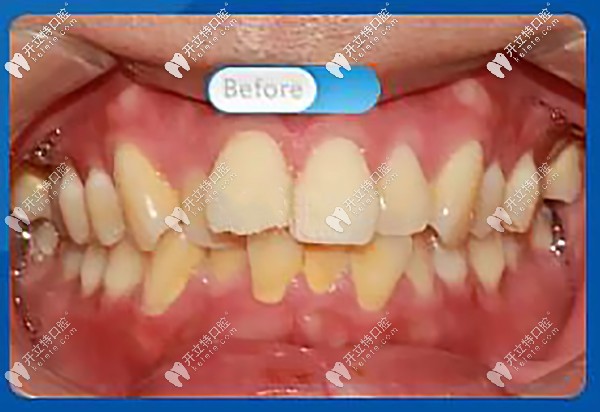

托槽矯正前,正面看牙齒屬于重度擁擠,微笑時,明顯看到前牙凸出,凸嘴齙牙明顯

正面看牙齒屬于重度擁擠

側(cè)面顯凸嘴,唇型厚重,唇肌緊張

醫(yī)生:“從口內(nèi)正面照可以看到上牙列前牙前突,上下牙列不齊擁擠,牙中線不齊,上下咬合不協(xié)調(diào),磨牙深覆蓋?!?br/>

磨牙深覆蓋